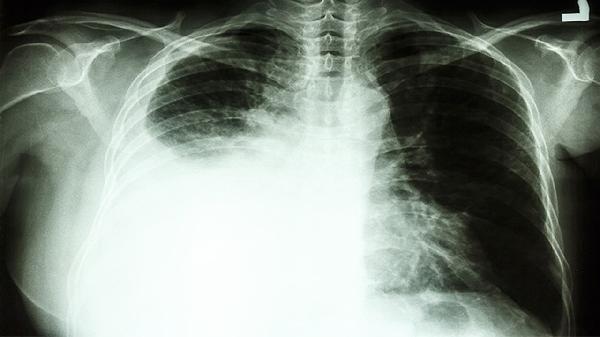

鸦胆子油软胶囊中的鸦胆子油酸等成分能干扰肿瘤细胞增殖周期,通过诱导细胞凋亡和抑制血管生成来减缓肺癌进展。临床多用于非小细胞肺癌的辅助治疗,常与化疗同步使用。需注意该药可能引起轻度胃肠不适,用药期间应定期复查影像学评估疗效。

对于肺癌引起的胸膜刺激性疼痛,该药可通过抗炎作用减轻神经压迫症状。部分患者用药后疼痛评分有所下降,但中重度疼痛仍需配合镇痛药物治疗。胸水明显者需结合胸腔穿刺引流。